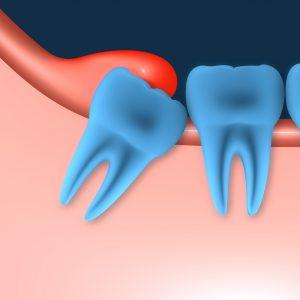

También ocurre con frecuencia que la vía de erupción sea correcta, pero que los maxilares sean demasiado pequeños para poder albergarlos.

Cuando esto ocurre, o bien no aparecen en boca, o bien se quedan a medio salir quedando la encía encima de estos como la visera de una gorra. Esta circunstancia provoca que se acumule mucha comida, placa bacteriana y suciedad entre la encía y la muela, aumentando el riesgo de sufrir caries, graves infecciones, dolor, inflamación de la mejilla, la aparición de pus y halitosis, mal aliento.

render muelas del juicio